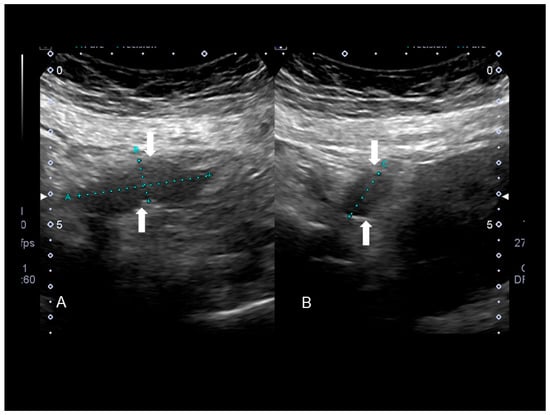

Figure 4. The ultrasonographic appearance of a Villar’s nodule (see white arrows) using B-mode (A) and color Doppler (B,C) with some color spots due to peripheral vascularization in a woman without previous abdominal surgery. In this case the ultrasonographic appearance was more cystic than solid (AC). The nodule at visual evaluation (D).

This umbilical endometriosis may appear as solid areas with ill-defined margins (Figure 3, Figure 4 and Figure 5) that can be irregular or spiculated [11], but more frequently than other endometriotic lesions they may have a cystic appearance (although Nuck nodules may also have this appearance) [18] (Figure 3, Figure 4 and Figure 5). In fact, the typical US finding is a nodular formation that occupies the umbilical scar, with ground-glass echogenicity, irregular margins, and no papillary structures with a detectable blood flow [7]. The absence of continuity with the deep fascial plane allows its differential diagnosis from invasive malignancies and hernias [18].